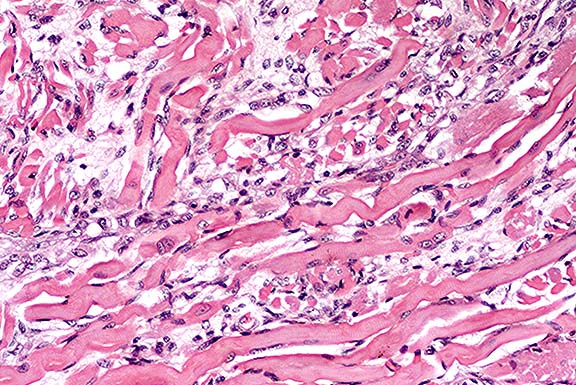

Case 11-2. Pancreas. Diffuse atrophy and fibrosis of the exocrine glands.

Histologic examination of the pancreas revealed diffuse acinar cell atrophy and loss. The remaining pancreas is composed primarily of variably sized aggregates of islet cells intermixed with pancreatic ducts surrounded by a moderately cellular fibrous connective tissue. There are a few scattered foci of fat necrosis and variable scattered collections of lymphocytes and plasma cells. The diffuse atrophy and fibrosis are most likely sequelae to chronic pancreatitis.

1. Pancreas: Atrophy, exocrine tissue, diffuse, severe, with fibrosis and minimal multifocal lymphocytic pancreatitis, chimpanzee (Pan troglodytes), primate.

2. Peripancreatic adipose tissue: Necrosis, multifocal.